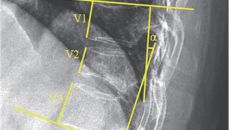

노인 골다공증성 압박 골절, 주사만으로 치료 효과 증명

[이데일리 이순용 기자] 노년층에서는 뼈가 약해져 작은 충격에도 골절을 입기 쉽다. 골절은 환자의 삶의 질을 감소시킬 뿐 아니- 2025-05-14 10:07